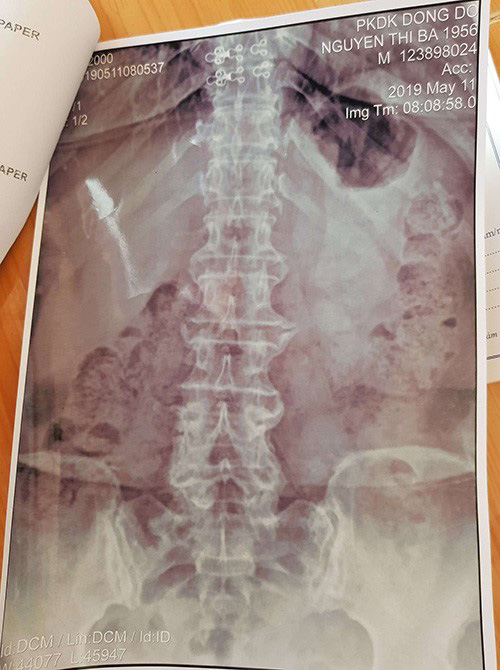

Phim chụp X-quang các đốt sống và khớp bị thoái hóa của bác Nguyễn Thị Ba